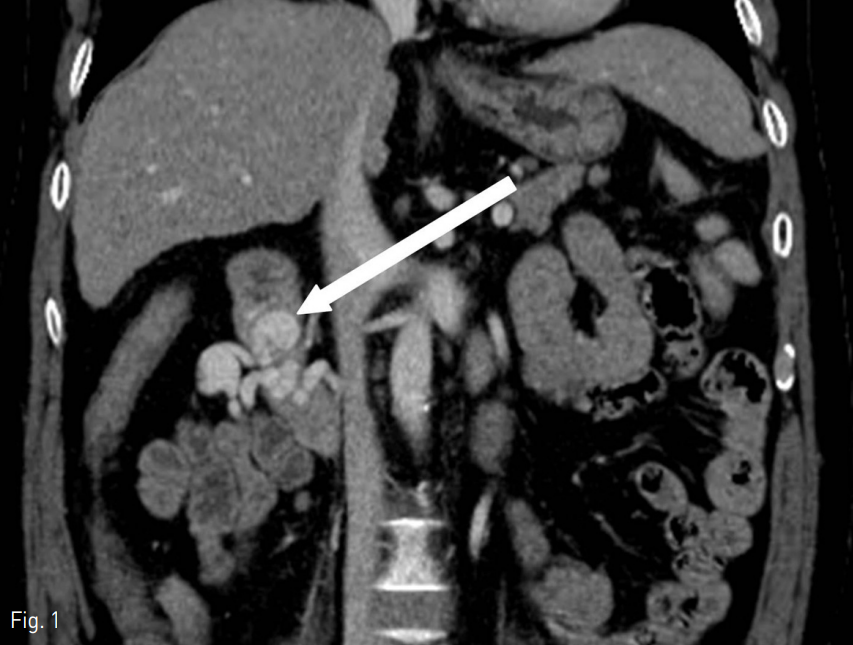

컴퓨터단층촬영상 최대 직경 약 2cm의 낭성 확장 두개를 포함한 정맥류가 십이지장 제이부에 관찰이 되었으나 활동성 출혈은 관찰되지 않았다 (Fig. 1).

Fig. 1

Contrast enhanced CT scan shows duodenal varices (white arrow).